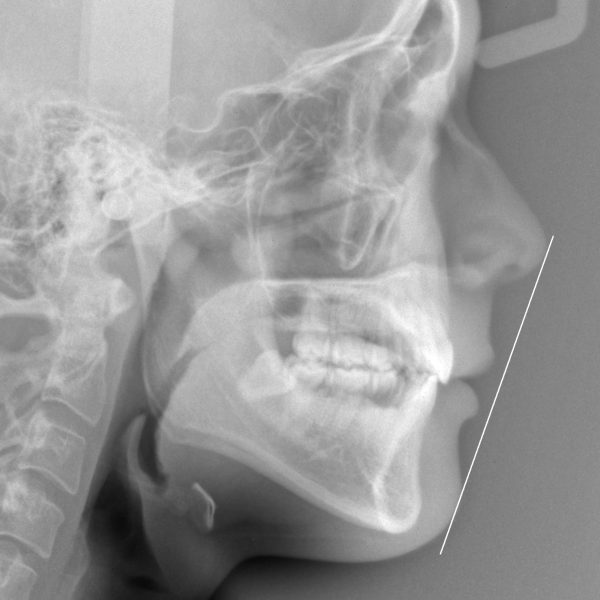

レントゲン写真を見てみると、

口ゴボ治療前

上下の歯が それぞれ前方に大きく傾斜して、前に押し出されています。

E-ラインからも上下口唇が 強く出てしまっています。

治療前後で前歯の傾斜がかなり改善しました。

レントゲン写真で確認しても上下の前歯は 大きく下がり、

口ゴボ治療後

前に飛び出していた上下の前歯の傾きが正常化しました。